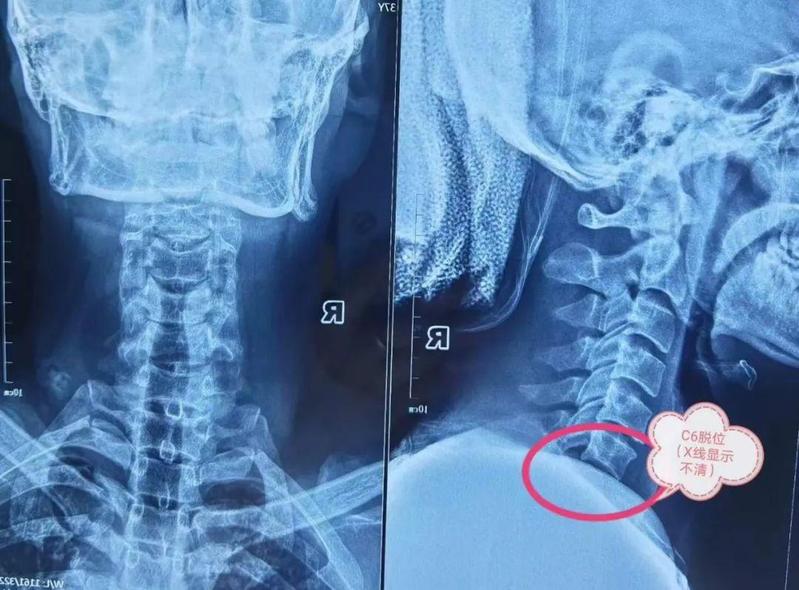

但由于肩胛骨的遮挡,在进行X光检查时

并未发现存在明显骨折、脱位

回家后,刘先生的症状没有任何缓解。由于行动不便、疼痛难忍,生活受到极大影响。为及时确诊病因,在朋友的力推下刘先生慕名来到罗医集团罗湖中医院脊柱骨科团队向陈晓东主任求助。经过陈晓东主任详细诊断,患者被确诊为颈椎骨折伴脱位,相应节段的脊髓受到压迫。

此类骨折的风险性极大,有很高的截瘫风险。经过严谨周密的病例讨论,脊柱骨科团队决定当即为刘先生予以颅骨牵引,通过头端牵引和手法提拉,但依然无法复位。